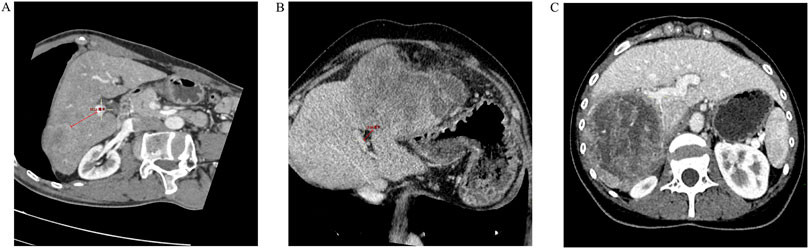

Aim: This study aims to explore the impact of the distance between the tumor and the main trunk or first branch of the portal vein on the prognosis of hepatocellular carcinoma (HCC) patients undergoing radical resection. Methods: This study retrospectively evaluated HCC patients who underwent radical resection between January 1, 2018, and September 30, 2024. Tumors are classified into two categories based on their location: central tumors and peripheral tumors. Central tumors are defined as those located within 2 cm of the main trunk or first branch of the portal vein, while the remaining tumors are classified as peripheral tumors. Recurrence free survival (RFS) and overall survival (OS) were compared between the two groups. Univariate and multivariate COX analyses were conducted to identify factors associated with RFS and OS. Propensity score matching (PSM) was employed to eliminate intergroup differences for further validation. Results: A total of 667 HCC patients undergoing radical resection were initially enrolled. Through propensity score matching, 247 patients were successfully matched in each comparative group. In the PSM cohort, the median RFS (mRFS) for patients with central tumors was 23.00 months (95% CI, 18.01-27.99 months), while the mRFS for those with peripheral tumors was 30.50 months (95% CI, 26.17-34.83 months) (p=0.004). The median OS was 56.00 months (95% CI, 52.10-59.90 months) for central tumors and 72.00 months (95% CI, 67.37-76.63 months) for peripheral tumors (p=0.043). Multivariate COX analysis confirmed that the distance of less than 2 cm between the tumor and the main trunk or first branch of the portal vein was an independent risk factor for RFS and OS in patients undergoing radical resection for HCC (HR: 1.744, p<0.001; 1.728, p<0.001, respectively). Conclusion: The distance of the tumor from the main portal vein trunk or its first branch correlates with the prognosis of hepatocellular carcinoma patients undergoing radical resection. Patients with tumors located ≤2 cm from the main trunk or first branch of the portal vein exhibited poorer RFS and OS.